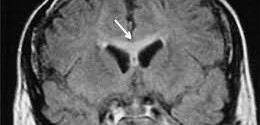

La Ataxia Espinocerebelosa (SCA3) se caracteriza por ataxia cerebelar progresiva. Como en todas las formas de ataxia, el primer síntoma normalmente es el deterioro de las capacidades para mantener el equilibrio, seguido después por incoordinación en las manos o dificultades en el habla (disartria). Algunos pacientes notan visión doble. Para el médico la apariencia de los ojos puede ser una …